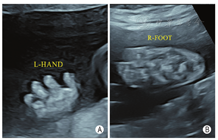

孕妇,21岁,孕4产0,孕27周。因外院羊水染色体核型分析提示47,XXX来我院行胎儿系统超声筛查。超声检查显示:胎儿生物学测量相当于孕23周+,胎儿面中部凹陷,鼻部短小,鼻梁低平,尾椎多个椎体融合、回声增强,左侧肱骨两端干骺端及双侧股骨近端干骺端可测及数个点状强回声斑(图1);双手掌及双足板短小,以指(趾)端明显,双手掌及双足板多个骨性结构短小、部分骨性结构未能显示(图2);胎儿阴蒂肥大(图3)。超声诊断:①宫内妊娠,中孕单活胎,相当于孕23周+;②胎儿面中部畸形、尾椎畸形、双侧股骨近端及肱骨两端点状强回声斑、双手及双足发育不良——Binder综合征可能;③胎儿外生殖器异常——阴蒂肥大;④胎儿宫内生长迟缓(intrauterine growth restriction,IUGR)。孕妇无华法林服用史等特殊病史,无酗酒史,维生素K依赖性凝血因子、凝血酶原时间正常。

Binder综合征又称上颌-鼻发育不良,是一种罕见的面中部先天性发育异常性疾病,面中部异常主要表现为鼻部短小,鼻背低平,鼻尖下垂,新月形鼻孔、眼距增宽、上颌骨发育不良并错颌畸形等[1]。产前超声表现:主要是在胎儿颜面正中矢状切面显示面中部扁平,包括鼻部短小、额部扁平、额鼻角异常增大、上颌骨平坦、下颌前突等;脊柱畸形是Binder综合征除颜面畸形外最常合并的畸形,包括椎体融合、椎体骨化不良等;长骨干骺端点状强回声斑也是Binder综合征常见的超声表现[2]。Binder综合征胎儿的染色体核型及基因检测多数未见异常,并且目前尚无明确致病基因用于Binder综合征的产前诊断[3]。正常胎儿约32周股骨远端出现次级骨化中心,约37周肱骨近端出现次级骨化中心。本病例为孕27周,具有面中部畸形、脊柱畸形、长骨干骺端点状强回声斑等典型胎儿Binder综合征超声表现,长骨干骺端点状强回声斑提示提前出现次级骨化中心、软骨发育不良可能。引产后标本面中部扁平、鼻梁及鼻翼周围平坦等表现与Binder综合征相符,全外显子组测序未见异常,最终确诊为Binder综合征。本例孕妇无华法林服用史、酗酒史等特殊病史,维生素K依赖性凝血因子、凝血酶原时间等未见明显异常,从而排除了该例Binder综合征是由维生素K缺乏引起。胎儿面中部扁平与50多种综合征相关,如点状软骨发育不良(punctate chondrodysplasia,CDP)、唐氏综合征、Apert综合征等,这些综合征中大多数均存在特征性改变,如Apert综合征特征性超声表现还包括尖头畸形、突眼、双侧对称性并指(趾)畸形等[4]。因此,当超声检查发现上述超声表现怀疑Binder综合征时,应与之相鉴别,尤其需要注意与CDP相鉴别。CDP是由染色体异常或基因突变引起的先天性酶代谢异常性疾病,产前超声表现除了与Binder综合征相似的面中部畸形,还包括脊柱侧弯、四肢不对称缩短等,行过氧化物酶等实验室检查及基因检测可与Binder综合征相鉴别[5]。本例患儿全外显子组测序未见异常,故排除CDP。对于染色体核型正常且孤立性面中部畸形的Binder综合征可通过出生后手术矫正,多数预后良好,合并其他系统复杂畸或合并染色体核型异常的的Binder综合征预后较差。